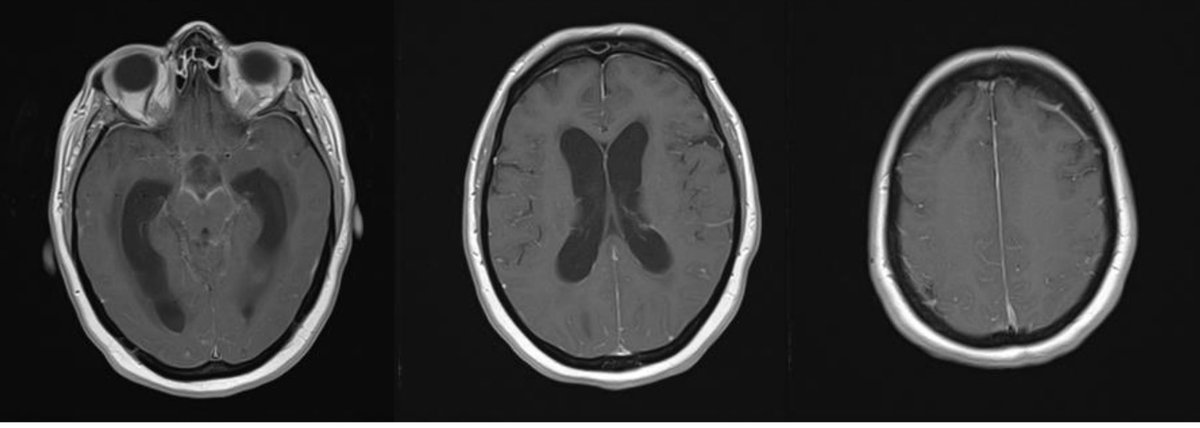

They undergo MRI brain, T1 post gad representative images shown. Patient with meningitis, ependymitis and ventriculitis & known communicating ๐Ÿง ๐Ÿ’ง (for the difference between communicating and non-communicating (aka obstructive) hydro, see: )

6/